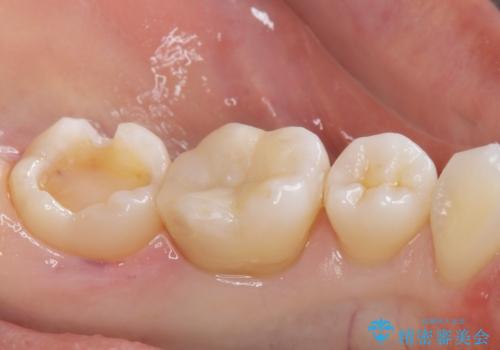

- メタルインレーが取れてしまって来院。

虫歯が再発していたので拡大鏡下で取り切った後、e-maxインレーにて治療しました。

また、一番奥の歯も古い樹脂の治療がされていたため虫歯の予防のために樹脂を取り除き、う蝕がないことを確認してe-maxインレーで治療しました。